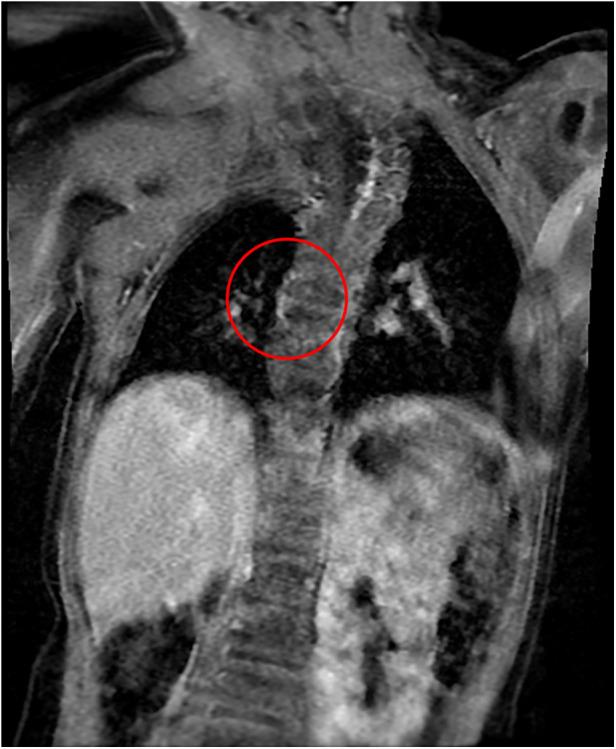

A girl with anorectal malformation and rectovestibular fistula, kidney malformation, and various vertebral defects came to our attention at the time of birth. VACTERL disease was diagnosed. She underwent Peña anoplasty at 4 months of life without complications. MRI was conducted at the age of 2. It accidentally showed a double esophageal duplication (12 mm × 35 mm × 10 mm) at the D7-D9 level. We planned a thoracoscopy; previous intraoperative esophagogastroduodenoscopy showed an external compression of the native esophagus. Two duplicated esophageal lesions were removed. The patient made an uneventful recovery and was completely asymptomatic at long-term follow-up.

一名患有肛门直肠畸形、直肠前庭瘘、肾脏畸形及多种脊柱缺陷的女婴在出生时引起了我们的注意。诊断为VACTERL病。她在4个月大时接受了佩尼亚肛门成形术,术后无并发症。2岁时进行了MRI检查,意外发现T7-T9水平存在双发性食管重复畸形(12 mm×35 mm×10 mm)。我们计划进行胸腔镜检查;之前的术中食管胃十二指肠镜检查显示原生食管受到外部压迫。切除了两个重复的食管病变。患者恢复顺利,长期随访完全无症状。